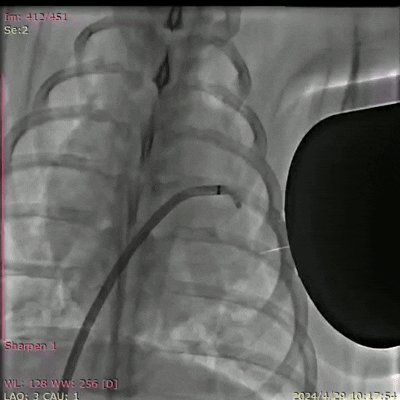

图3. DSA(数字减影血管造影)拍摄的巴马猪体内磁流体左心耳封堵实验过程(动图请看附件)。凯发k8国际供图